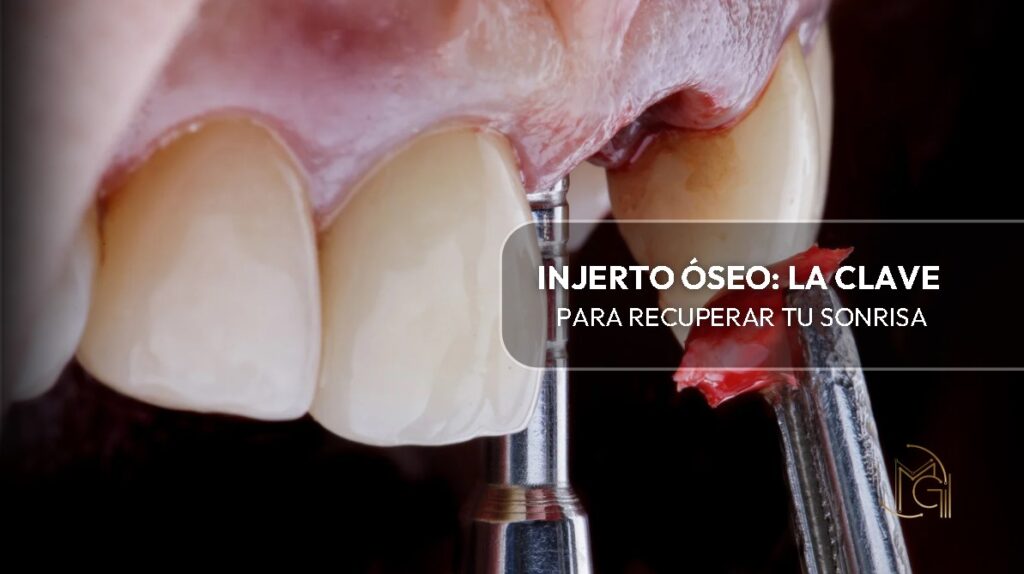

Injerto óseo: la clave para recuperar tu sonrisa

¿Sabías que, así como un edificio necesita una base sólida, tus dientes también dependen de una estructura firme debajo de ellos? Esa base es el hueso, y en algunos casos, puede debilitarse o incluso perderse. ¿La buena noticia? Hoy en día contamos con una técnica confiable y segura llamada injerto óseo, que nos permite regenerar y fortalecer esa estructura ósea perdida.

Uno de los términos que más despierta curiosidad cuando hablamos de cirugía oral es “injerto óseo”. Y es completamente normal, porque no todos los días escuchamos sobre procedimientos que involucran reconstruir hueso dentro de la boca o el rostro. Pero te aseguro que es más común de lo que imaginas, y también más seguro de lo que parece.

Se trata de un procedimiento quirúrgico mediante el cual colocamos material óseo (natural o sintético) en una zona donde hay pérdida o deficiencia de hueso. Este “material de refuerzo” actúa como un andamio que permite al organismo regenerar hueso nuevo en esa área específica. Es decir, nos ayuda a restaurar estructura, volumen y soporte óseo, sobre todo en la mandíbula y el maxilar.

En odontología, el injerto óseo es fundamental cuando queremos colocar un implante dental pero no existe suficiente hueso para sostenerlo de manera estable. También es útil después de una extracción dental, para prevenir que el hueso se reabsorba, o en casos donde hay enfermedades como la periodontitis que han deteriorado la base ósea.